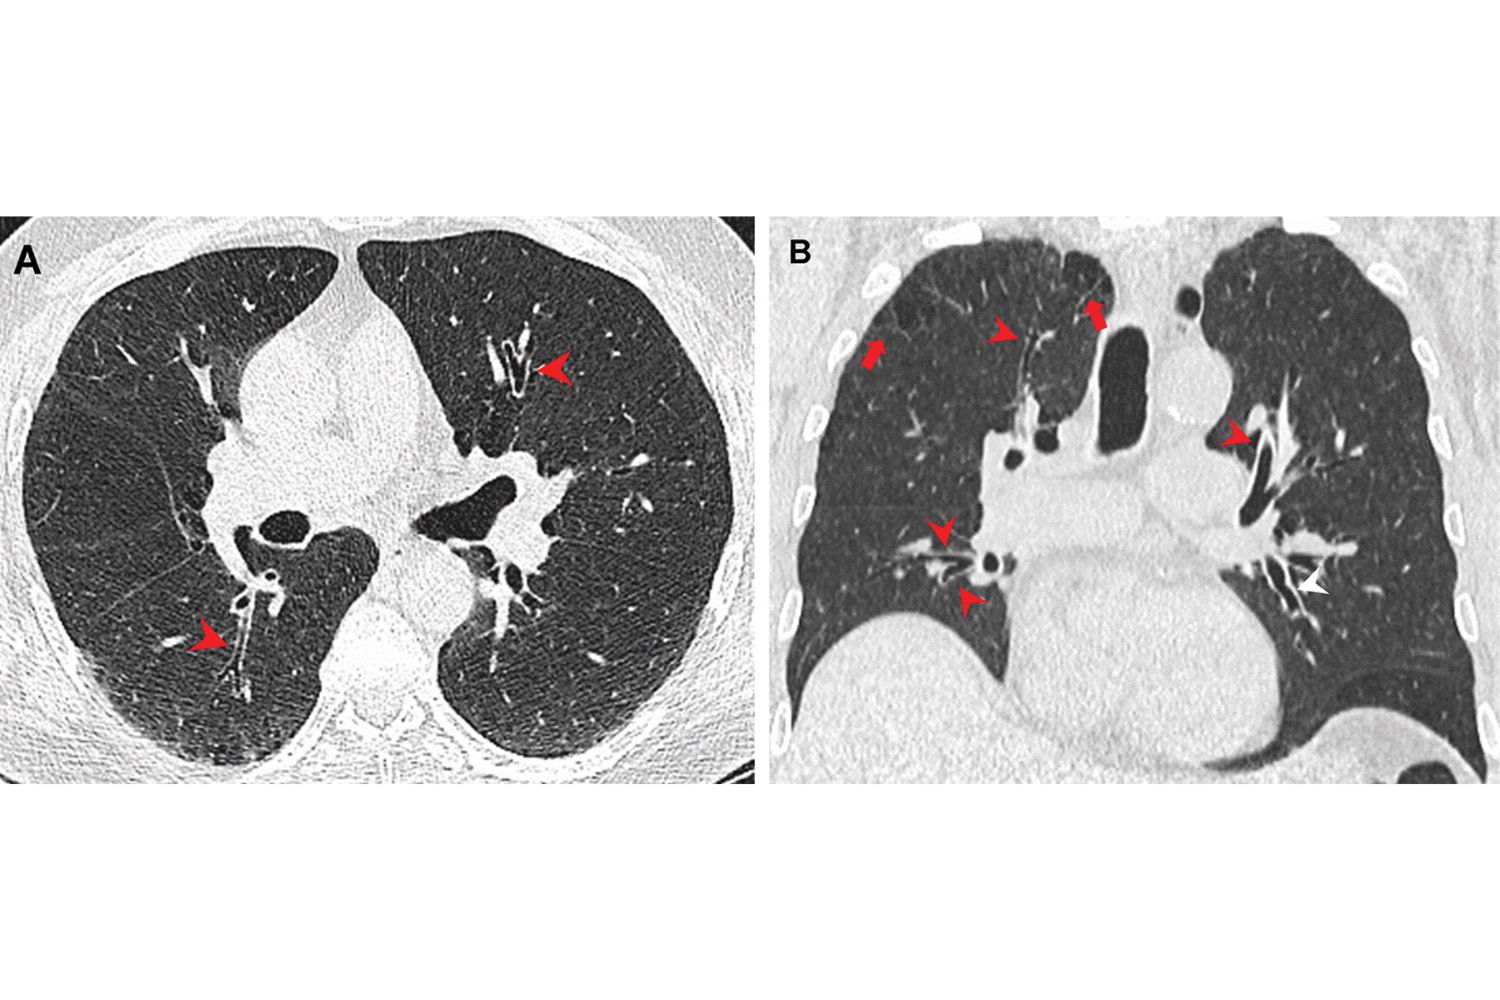

Smoking marijuana may be more harmful to lungs than cigarettes, study says

Smoking marijuana may be more harmful to smoker’s lungs than tobacco, new study finds